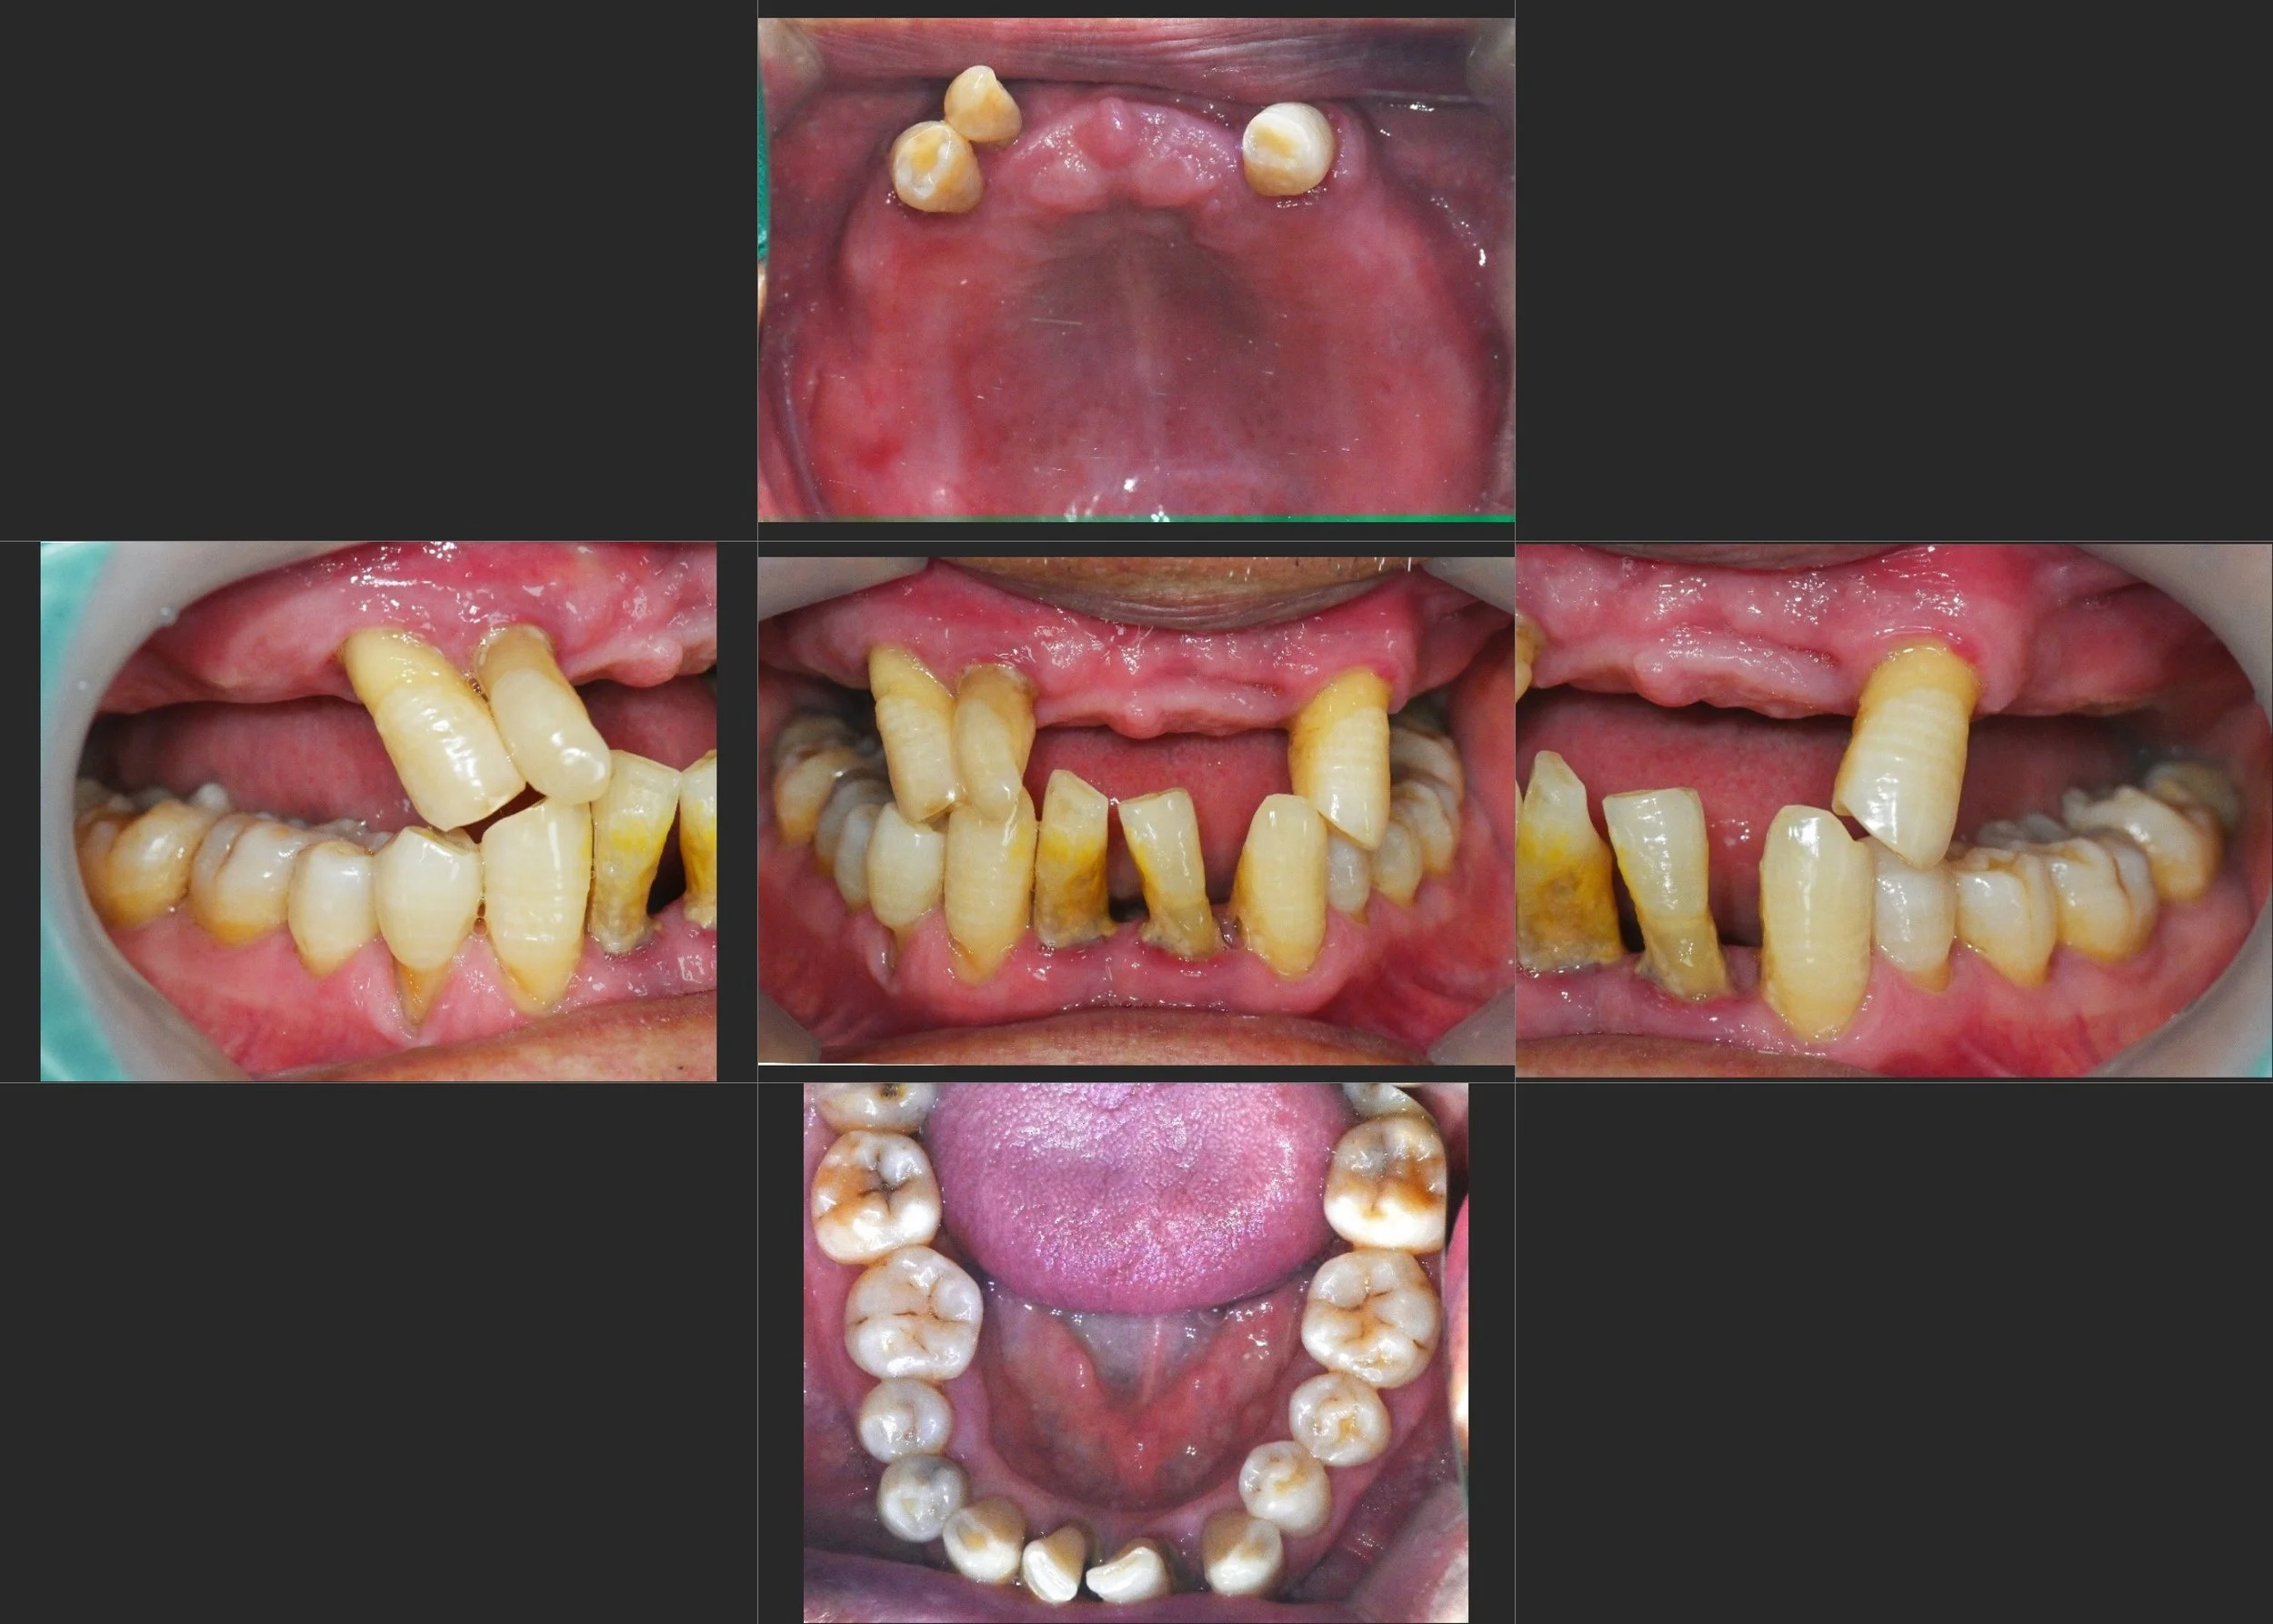

The patient presented with collapse of abutment teeth caused by long-standing use of an ill-fitting removable denture.

While the maxillary dentition showed significant deterioration, the mandibular posterior teeth remained relatively well preserved.

Due to financial considerations, full-arch rehabilitation was not a viable option, and a pragmatic treatment compromise was required.

INTRA ORAL - BEFORE